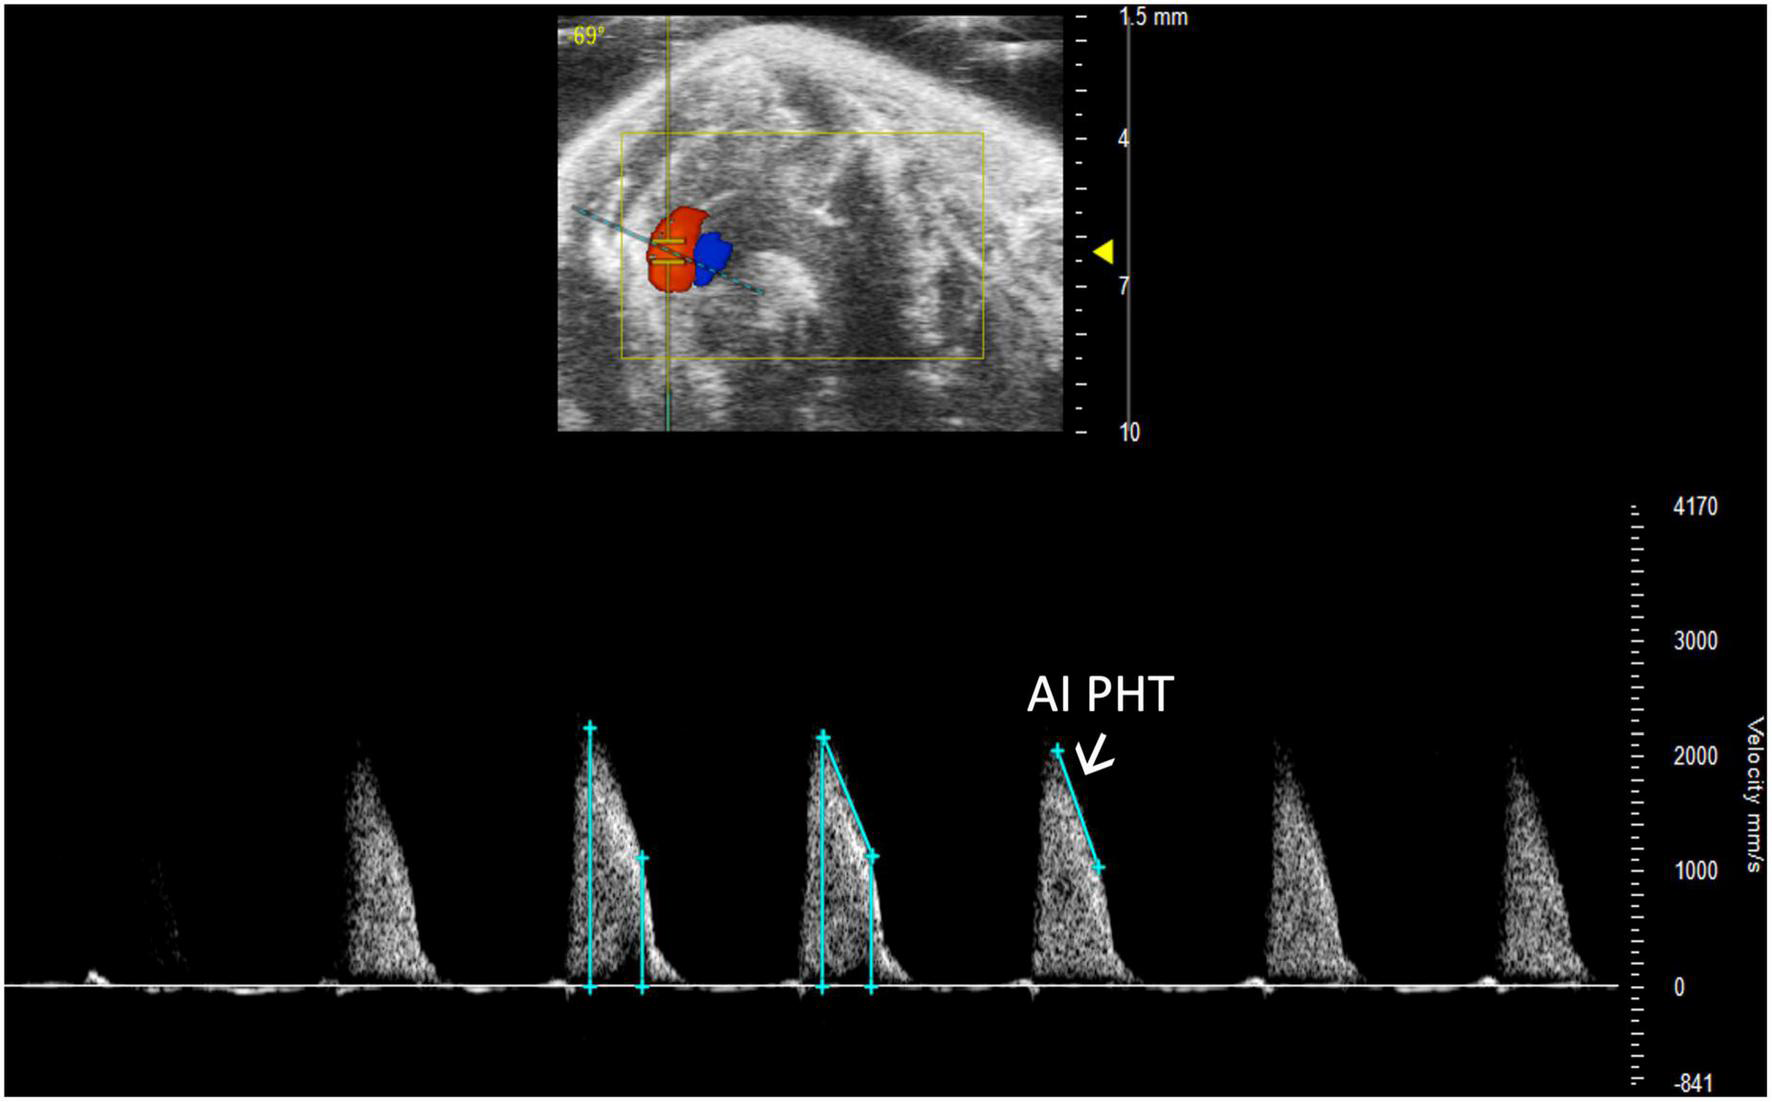

2.3.4.1 Aortic insufficiency deceleration

Aortic insufficiency pressure half time (AI PHT) is the rate of deceleration of Doppler signal, indicating the degree of regurgitation and LVEDP (13). The same method to measure MV PHT is used to measure AI PHT in PW Doppler mode of the aortic valve (Figure 13). Aortic insufficiency half time is automatically calculated.

FIGURE 13

Aortic insufficiency pressure half time (AI PHT) represents the degree of regurgitation and reflects the left ventricular end diastolic pressure and is measured in pulsed wave (PW) Doppler mode of the aortic valve.